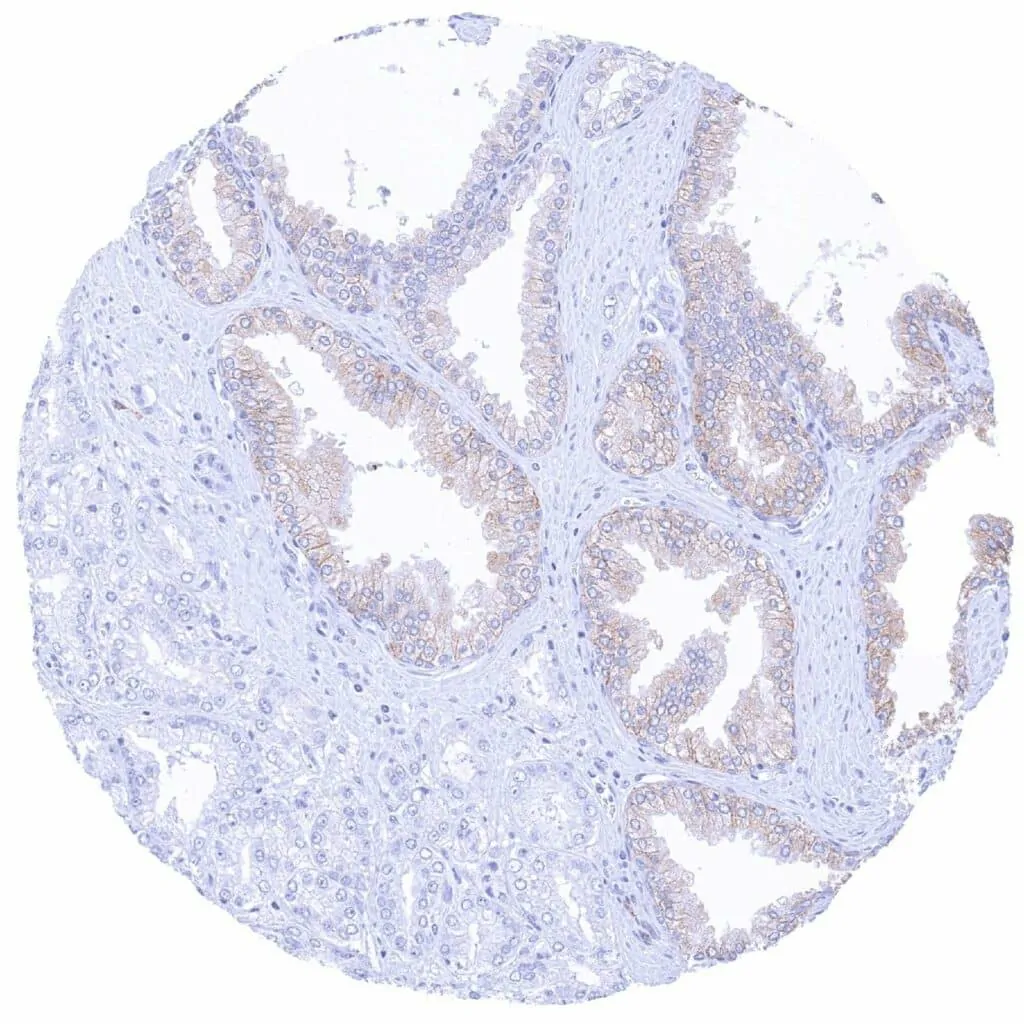

Kidney – CD38 negative papillary renal cell carcinoma